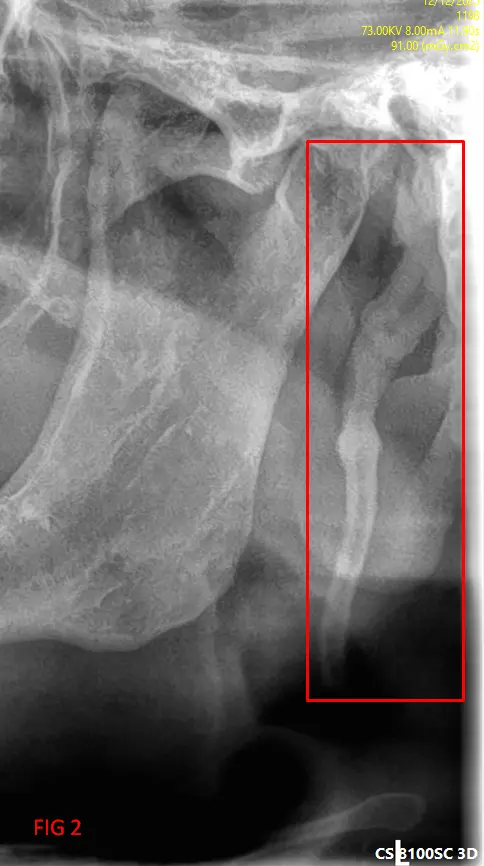

En el análisis de la ortopantomografía, se identifican estructuras radiopacas bilaterales de morfología alargada. Estas formaciones se extienden desde la base del cráneo (apófisis estiloides) con una trayectoria descendente y anterior hacia el hueso hioides (FIG 1, 2 y 3). Basándose en las características imagenológicas, se concluye que se trata de una osificación bilateral del ligamento estilohioideo, un hallazgo que suele presentarse de forma incidental